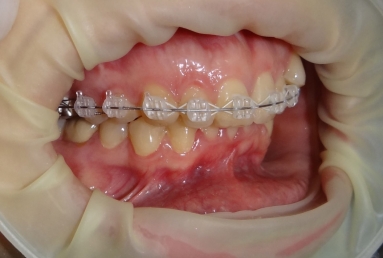

SAPPHIRE ORTHODONTIC DEVICE

Orthodontic treatment, external sinus lifting, dental implant and zirconium crown.